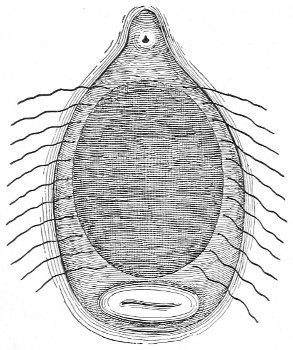

The Vaginal Speculum.—The speculum is an instrument through which a visual examination is made of the vagina, the external os uteri, and the vaginal cervix. A 29 great number of specula have been invented. At the present day the best two instruments of this class are the bivalve speculum, such as Goodell’s (Fig. 6), and the duck-bill speculum (Fig. 7), or perineal retractor, invented by Sims.

Fig. 6.—Goodell’s speculum.

The bivalve speculum is introduced with the woman upon her back, in the dorso-sacral position already described. The vulva and the vagina should be cleaned. The speculum should be warmed by placing it in hot water, and should then be lubricated with the soap solution or with vaseline. It should be introduced with the blades closed and the plane of the blades lying not exactly 30 in the median sagittal plane of the body, but inclined at a small acute angle to this plane, one edge of the speculum being directed toward either vaginal sulcus. The instrument is passed into the vagina toward the position in which, by a previous digital examination, the vaginal cervix had been found to lie. The instrument is then turned with the handles toward either thigh, so that the blades become parallel to the anterior and posterior vaginal walls, in order that, when separated, they will open the vaginal slit. The handles are brought together and the blades opened. When the vaginal cervix comes well into view the blades are fixed in place by the screws (Fig. 9).

Fig. 9.—Goodell’s speculum in position.

By means of the bivalve speculum we are able to make a partial inspection of the vaginal walls, an imperfect inspection of the vaginal vault, and a good inspection of the vaginal cervix and the external os. Applications 31 can be made to the cervix, but none of the minor operations of gynecology can be performed through this speculum.